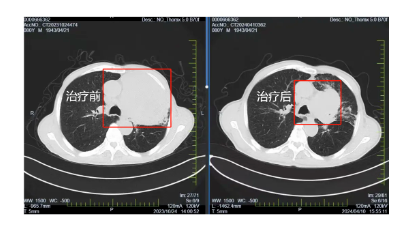

在國(guó)文醫(yī)院胸部腫瘤放化療Ⅲ病區(qū)醫(yī)護(hù)人員的精心照料和密切監(jiān)測(cè)下,患者經(jīng)過6周期的免疫治療,肺部腫瘤明顯縮小,一年間由原來的95x90mm降至70x50mm,腫瘤明顯縮小且腫瘤內(nèi)見壞死及空洞。張大爺?shù)纳眢w狀況也逐漸好轉(zhuǎn),原本因癌細(xì)胞壓迫導(dǎo)致的呼吸困難癥狀得到了明顯緩解,能夠進(jìn)行一些簡(jiǎn)單的日;顒(dòng),張大爺?shù)哪樕嫌种匦戮`放出笑容。